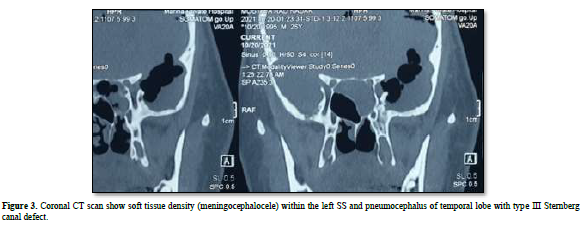

Case description: A 27-year-old male, presented with left cerebrospinal fluid (CSF) rhinorrhea, referred from the neurosurgical department with severe headache, and low-grade fever. Radiological investigations consisted of computed Tomography (CT) scan, this imaging study identified a soft tissue density Through a bony defect which communicates the middle cranial fossa with the lateral recess of the SS, and pneumocephalus of left temporal lobe. Patient underwent an Endoscopic Endonasal repair of the defect. There was no complication related to the surgical procedure and no recurrence of CSF leakage occurred 4 months after surgery.

A computed tomography (CT) scan revealed a defect in the middle cranial fossa communicated to the lateral recess of the left Sphenoid Sinus and a soft tissue density within the sinus, with air void signal extended in to the left temporoparietal and frontal hemisphere (Figures 1-4). It appeared to be due to persistence of the Sternberg’s canal.